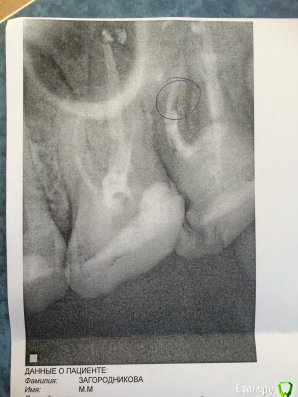

maria_zag Опубликовано 28 июля, 2017 Поделиться Опубликовано 28 июля, 2017 Здравствуйте! Несколько дней назад заболел зуб(семерка), рядом растет зуб мудрости, списала боль на растущую восьмерку, но, посещение врача прояснило ситуацию. Стоматолог, сделав снимок, заключил, что у меня сломался корень зуба и восстановить его невозможно, только удаление. Что можно сказать по снимку? И действительно ли единственным выходом является удаление? Ссылка на комментарий

DmitrySH Опубликовано 29 июля, 2017 Поделиться Опубликовано 29 июля, 2017 На основании данного снимка сложно утверждать о переломе корня Ссылка на комментарий